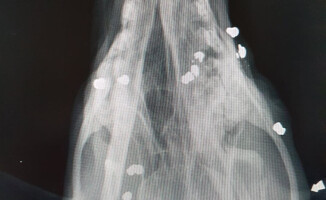

Ktoś strzelał z wiatrówki do bezdomnego psa tak długo, aż ten stracił wzrok i nie mógł dalej uciekać. W ciele czworonoga weterynarze znaleźli około 50 pocisków. Połowa z nich tkwi w okolicach czaszki.

Rannego psa znaleziono w okolicach Czarnkowa pod koniec czerwca. Wyglądał tak, jakby uległ wypadkowi. Początkowo przewieziono zwierzę do schroniska Azorek w Obornikach. Po udzieleniu pierwszej pomocy, zgodnie z procedurami, schronisko przekazało psa do lekarza weterynarii, z którym gmina ma podpisaną umową. Prześwietlenia pokazały, że w samej głowie zwierzęcia tkwi 26 pocisków. Po dalszych badaniach weterynarze znaleźli jeszcze ponad dwadzieścia.

fot. schronisko Azorek w Obornikach